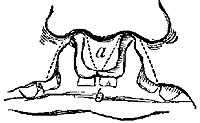

The four plates which precede the letterpress were drawn on wood (from original photographs) by Mr. D.W. Williamson, Melbourne Place, and the lines of incision for the various operations were added by the author.

The rough woodcuts scattered through the work were drawn on wood by the author, and for their roughness he, not his engraver, is responsible. He also hopes that the references in the letterpress will be accepted as sufficient acknowledgment of the true ownership, in those few instances in which the idea of the diagram has been borrowed.